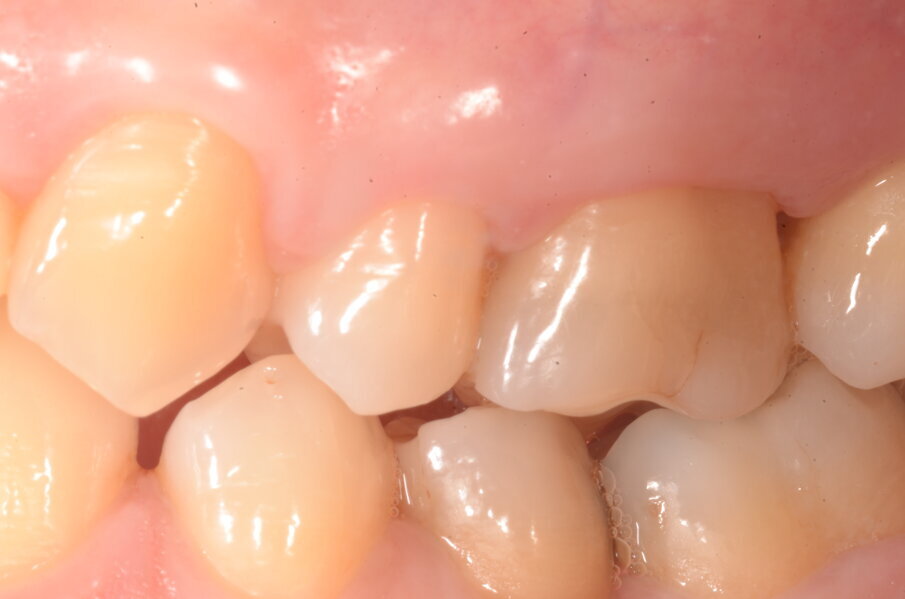

Figg. 6k-6m - Guarigione ad 1 mese.

La guarigione è avvenuta senza complicanze e senza segni di deiscenza o esposizione della membrana (Figg. 6h-l). Anche in questo secondo caso le caratteristiche di ottima integrazione della membrana si sono rese evidenti. Il caso è presentato con follow up a 6 mesi (Figg. 6m-6p), a breve avremo i valori e gli indici ad un anno.